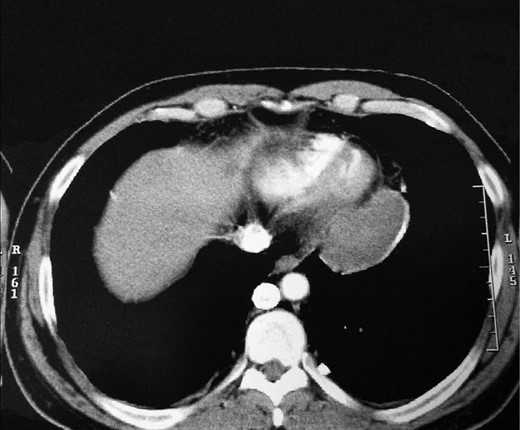

Investigations initially showed a normal full blood count and a positive Casoni test. A chest CT scan with contrast subsequently revealed two multi-loculated mediastinal cysts. The first was located in the middle mediastinum lateral to the ascending aorta. The second was posterior to the heart attached to the posterolateral surface of the left ventricle (Fig. 1). Echocardiography demonstrated that the posterior cyst was adherent to the posterior surface of the left ventricle.